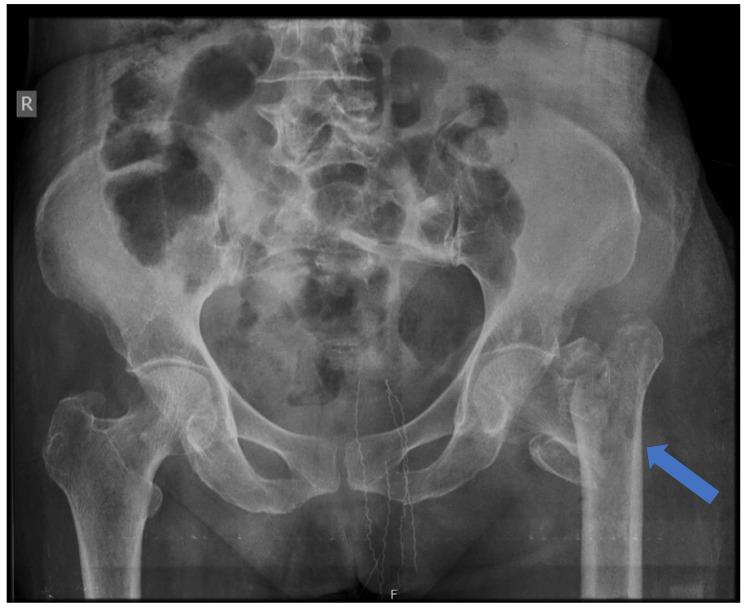

采用带股骨距柄的双极半髋关节置换术治疗老年不稳定型股骨转子间骨折中股骨近端抗旋髓内钉-亚洲型(PFNA2)失败病例

Intertrochanteric (IT) femur fractures in the elderly population comprise a major part of geriatric trauma and fractures. There are various modalities of surgical management, ranging from intramedullary fixation and extramedullary fixation to even replacing the hip joint. Apart from the surgeon's choice, other factors, such as geriatric age, bone quality and osteoporosis, medical comorbidities, life expectancy, pre-operative ambulatory status, muscle strength, type and pattern of fracture, and mental health of the patient, play vital roles in determining the ideal modality of management and the long-term outcome. The present case is a 75-year-old lady who had an IT fracture due to a domestic fall, managed surgically with a proximal femoral nail anti-rotation Asia (PFNA2) for an unstable fracture. She presented with blade back-out on the 11th day postoperatively. The patient was investigated thoroughly, and infection was ruled out. She was managed by the removal of the nail, followed by a cemented calcar-replacing bipolar hemiarthroplasty for an unstable comminuted IT fracture. The patient was ambulatory with a walker by the seventh postoperative day and without a walker by the sixth week, and she was self-sufficient in her activities of daily living. Every geriatric IT fracture must be evaluated thoroughly for contributing factors, such as osteoporosis and fracture pattern, to predict outcomes, and a tailor-made strategy of surgical management and stepwise physiotherapy must be provided to the patient for the best results.

老年人群中的股骨粗隆间骨折是老年创伤和骨折的主要组成部分。手术治疗方式多种多样,从髓内固定、髓外固定到甚至髋关节置换。除了外科医生的选择外,其他因素,如老年年龄、骨质质量和骨质疏松症、合并症、预期寿命、术前活动状态、肌肉力量、骨折类型和形态以及患者的心理健康,在确定理想的治疗方式和长期预后方面起着至关重要的作用。本病例是一位75岁的女性,因在家中跌倒导致股骨粗隆间骨折,对于不稳定骨折采用股骨近端抗旋髓内钉亚洲版(PFNA2)进行手术治疗。她在术后第11天出现刀片退出。对患者进行了全面检查,排除了感染。通过取出髓内钉对其进行治疗,随后针对不稳定的粉碎性股骨粗隆间骨折进行了骨水泥型股骨距替代双极半髋关节置换术。患者术后第7天借助助行器可行走,术后第6周无需助行器,并且在日常生活活动中能够自理。每一例老年股骨粗隆间骨折都必须对骨质疏松症和骨折形态等促成因素进行全面评估,以预测预后,并且必须为患者提供量身定制的手术治疗策略和逐步的物理治疗,以获得最佳效果。